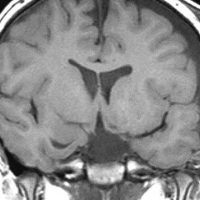

幼児期に思春期早発で発症

思春期早発で発症した幼児の視床下部過誤腫

視神経交叉の後方,乳頭体の前からぶら下がるようにしてあります

典型的な有茎状タイプです